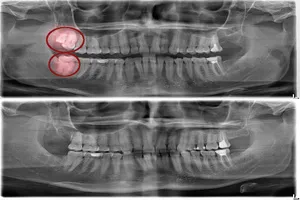

3. 복잡 매복 발치 (뼈 속에 묻힌 경우)

턱뼈 속에 깊이 묻혀 있거나, 신경과 가깝게 위치하거나, 옆으로 누워 자라는 등 비정상적인 형태의 사랑니는 발치 난이도가 매우 높습니다. 뼈를 삭제하거나 사랑니를 여러 조각으로 나누어 제거해야 하는 고난도 수술이 필요하므로 비용이 가장 높습니다. 건강보험 적용 시 5만 원 ~ 10만 원 이상의 본인 부담금이 발생할 수 있으며, 난이도가 아주 높거나 특수한 경우에는 그 이상으로 증가할 수도 있습니다.